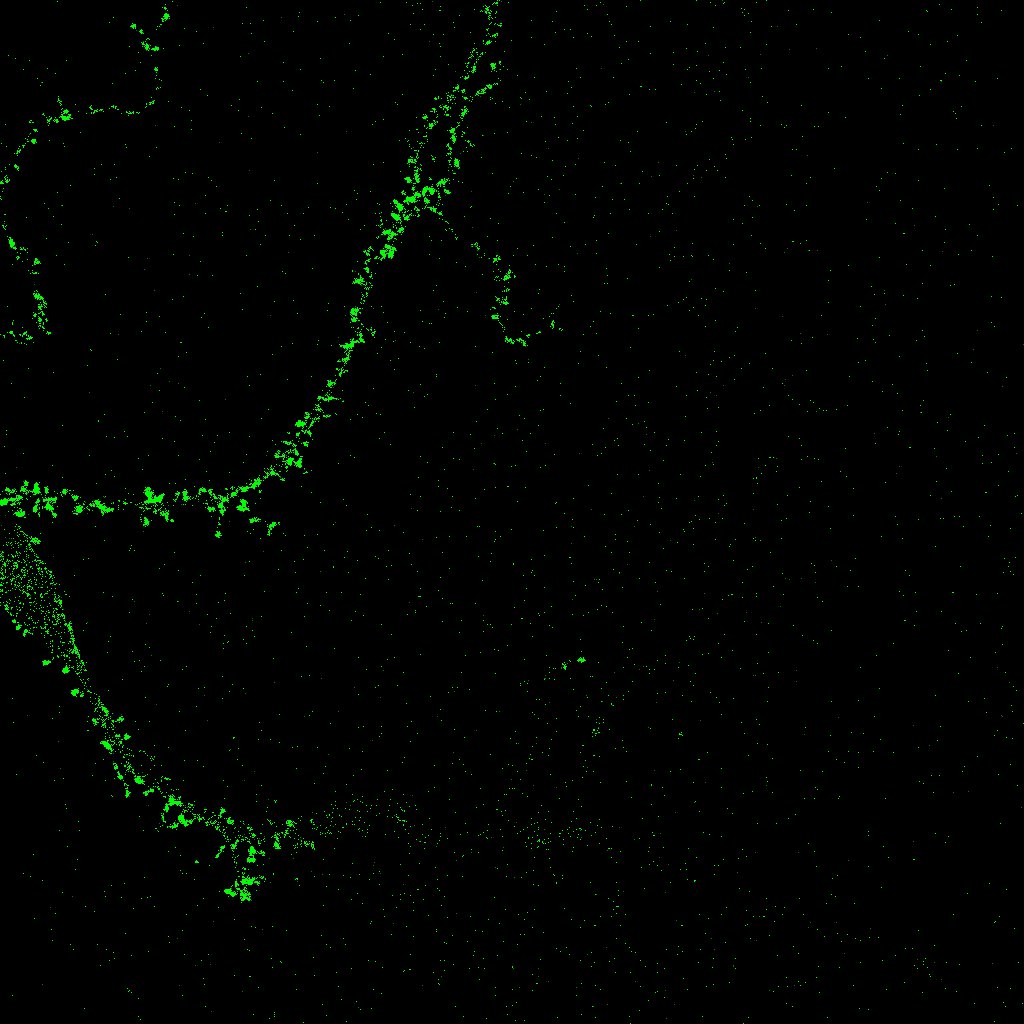

El primer plugin que desarrollamos se denomina SynapCountJ [13], y se utiliza para calcular el número de sinapsis que aparecen en la imagen de una neurona. Como ya se ha comentado anteriormente, el programa recibe dos imágenes diferentes de la misma neurona tomadas en un momento concreto tras la aplicación de dos marcadores, en rojo y verde. El usuario debe señalar manualmente la región en la que va a realizarse la medida, esto es, las distintas ramas (dendritas) de la neurona, lo que nos da una tercera imagen en azul (para esta parte hacemos uso del plugin NeuronJ [17]). Con estos datos, el programa marcará como sinapsis los puntos de rojo, verde y azul que coincidan en las tres imágenes (y que aparecerán como puntos blancos, véase la figura 1). El usuario puede modificar los parámetros introduciendo el rango tanto de rojo como de verde que considera que debe poseer una sinapsis. Según se va eligiendo el rango se pueden ir observando la zonas de la neurona que se van a marcar como sinapsis para hacer una mejor estimación. Finalmente, el programa presenta la imagen con las sinapsis señaladas y muestra también una tabla en la que se indican el número de sinapsis y la densidad obtenida. Véanse las dos imágenes de partida y el resultado dado por SynapCountJ (las tres en escala de grises) en la figura 8. En esta imagen las sinapsis corresponden a los puntos más oscuros dentro de la zona señalada.

Refer to captionRefer to captionRefer to caption

Figura 8: Resultado de SynapCountJ

Uno de los conceptos más importantes para nuestro trabajo es la noción de conexión, o más concretamente, el cálculo del número de componentes conexas. Ésta es la idea fundamental empleada para el recuento de sinapsis en una imagen de cultivo: tras solapar dos imágenes diferentes de la misma neurona en un mismo instante obtenidas tras la aplicación de dos marcadores primarios y señalar manualmente la región en la que debe realizarse la medida, las distintas sinapsis corresponden a las componentes conexas obtenidas en la intersección. El programa realiza este cálculo, marca sobre la imagen las distintas apariciones y nos da el número total de sinapsis (componentes conexas) localizadas.

Para la automatización de los procesos llevados a cabo por el grupo PSE, se planteó en primer lugar el problema del cálculo del número de sinapsis, que son los puntos de conexión entre las neuronas. Las sinapsis tienen una gran importancia en el campo de investigación tratado ya que están relacionadas con las capacidades de cálculo del cerebro, y la posibilidad de incrementar el número de contactos sinápticos puede ser una ventaja importante en el tratamiento de enfermedades neurodegenerativas. Para realizar el recuento de sinapsis se necesitan dos imágenes diferentes de la misma neurona que se obtienen usando técnicas de laboratorio, más concretamente utilizando dos marcadores que reconocen estructuras sinápticas; esas dos imágenes se superponen y se realiza el recuento de las sinapsis. En la figura 1, de tamaño 1024×1024102410241024\times 1024 píxeles, o equivalentemente 228×228228228228\times 228 micras, las sinapsis son los puntos que aparecen en blanco.